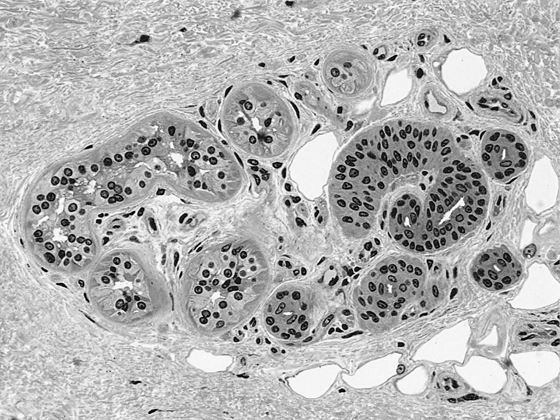

Микроскопический срез эккриновых желез человека

Первое преимущество связано с тем, как мы дышим. Четвероногие могут делать только один вдох за цикл движений, потому что их грудная клетка должна абсорбировать удар о землю передних конечностей. Но мы можем выбирать другое соотношение, и это позволяет нам более рационально использовать энергию. Второе (и более существенное) преимущество заключается в непревзойденной способности регулировать температуру тела, что позволяет нам делать то, чего не могут львы: долго и быстро бежать на полуденной жаре.

Все дело в потоотделении. Два крупных животных, которые служат нам транспортом, потеют гораздо сильнее других четвероногих: за час лошадь может потерять около 100 г воды на квадратный метр кожи, а верблюд – до 250 г/м2. Человек способен без труда выделить 500 г/м2, и этого хватит для отвода тепловой мощности от 550 до 600 Вт. Пиковое потоотделение за час может превышать 2 кг/м2, а максимальный зарегистрированный уровень потоотделения за короткий период еще в два раза выше.